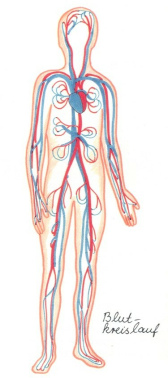

Demgegenüber kann metallisches Quecksilber als Dampf über

die Atmungsorgane praktisch vollständig resorbiert werden.

Ein hoher Anteil (ca. 80 %) des resorbierten

Quecksilberdampfes gelangt aus der Lunge ins Blut (Schäfer

et al. 1994; Gerstner / Huff 1977). Eine zusätzliche

Hg-Kontamination des Blutes als Folge von Hg-Dampf erfolgt

über den Magen-Darm-Kanal: Hg-Dampf kann im Speichel

gelöst oder in feinverteilter Form verschluckt und aus dem

Magen-Darm-Kanal mit einer beträchtlichen, nicht näher

bekannten Resorptionsquote in die Blutbahn aufgenommen

werden (Ohnesorge 1982, abgedr. [abgedruckt] auch 1992).

Im Blut wird der resorbierte Hg-Dampf in den Erythrozyten

[rote Blutkörperchen] gebunden. Der überwiegende Anteil

wird durch das Enzym Katalase zu zweiwertigen Hg-Ionen (Hg

2+)

oxidiert (Schaller et al. 1994; Berlin 1986; Hursh 1985;

Clarkson et al. 1980) und verteilt sich dann wie diese

(Strubelt et al. 1988; siehe unten b)). Der nicht

oxidierte Teil des resorbierten Hg-Dampfes wird über die

Blutbahn zu allen Organen transportiert (Gloxhuber 1994).

Er wird dort zu Hg

2+ oxidiert

und als solches in den Organen gebunden.

|

Das Blut

nimmt Quecksilber aus Quecksilberdämpfen auf,

und so kann jedes Organ durch

Quecksilberdämpfe geschädigt werden.